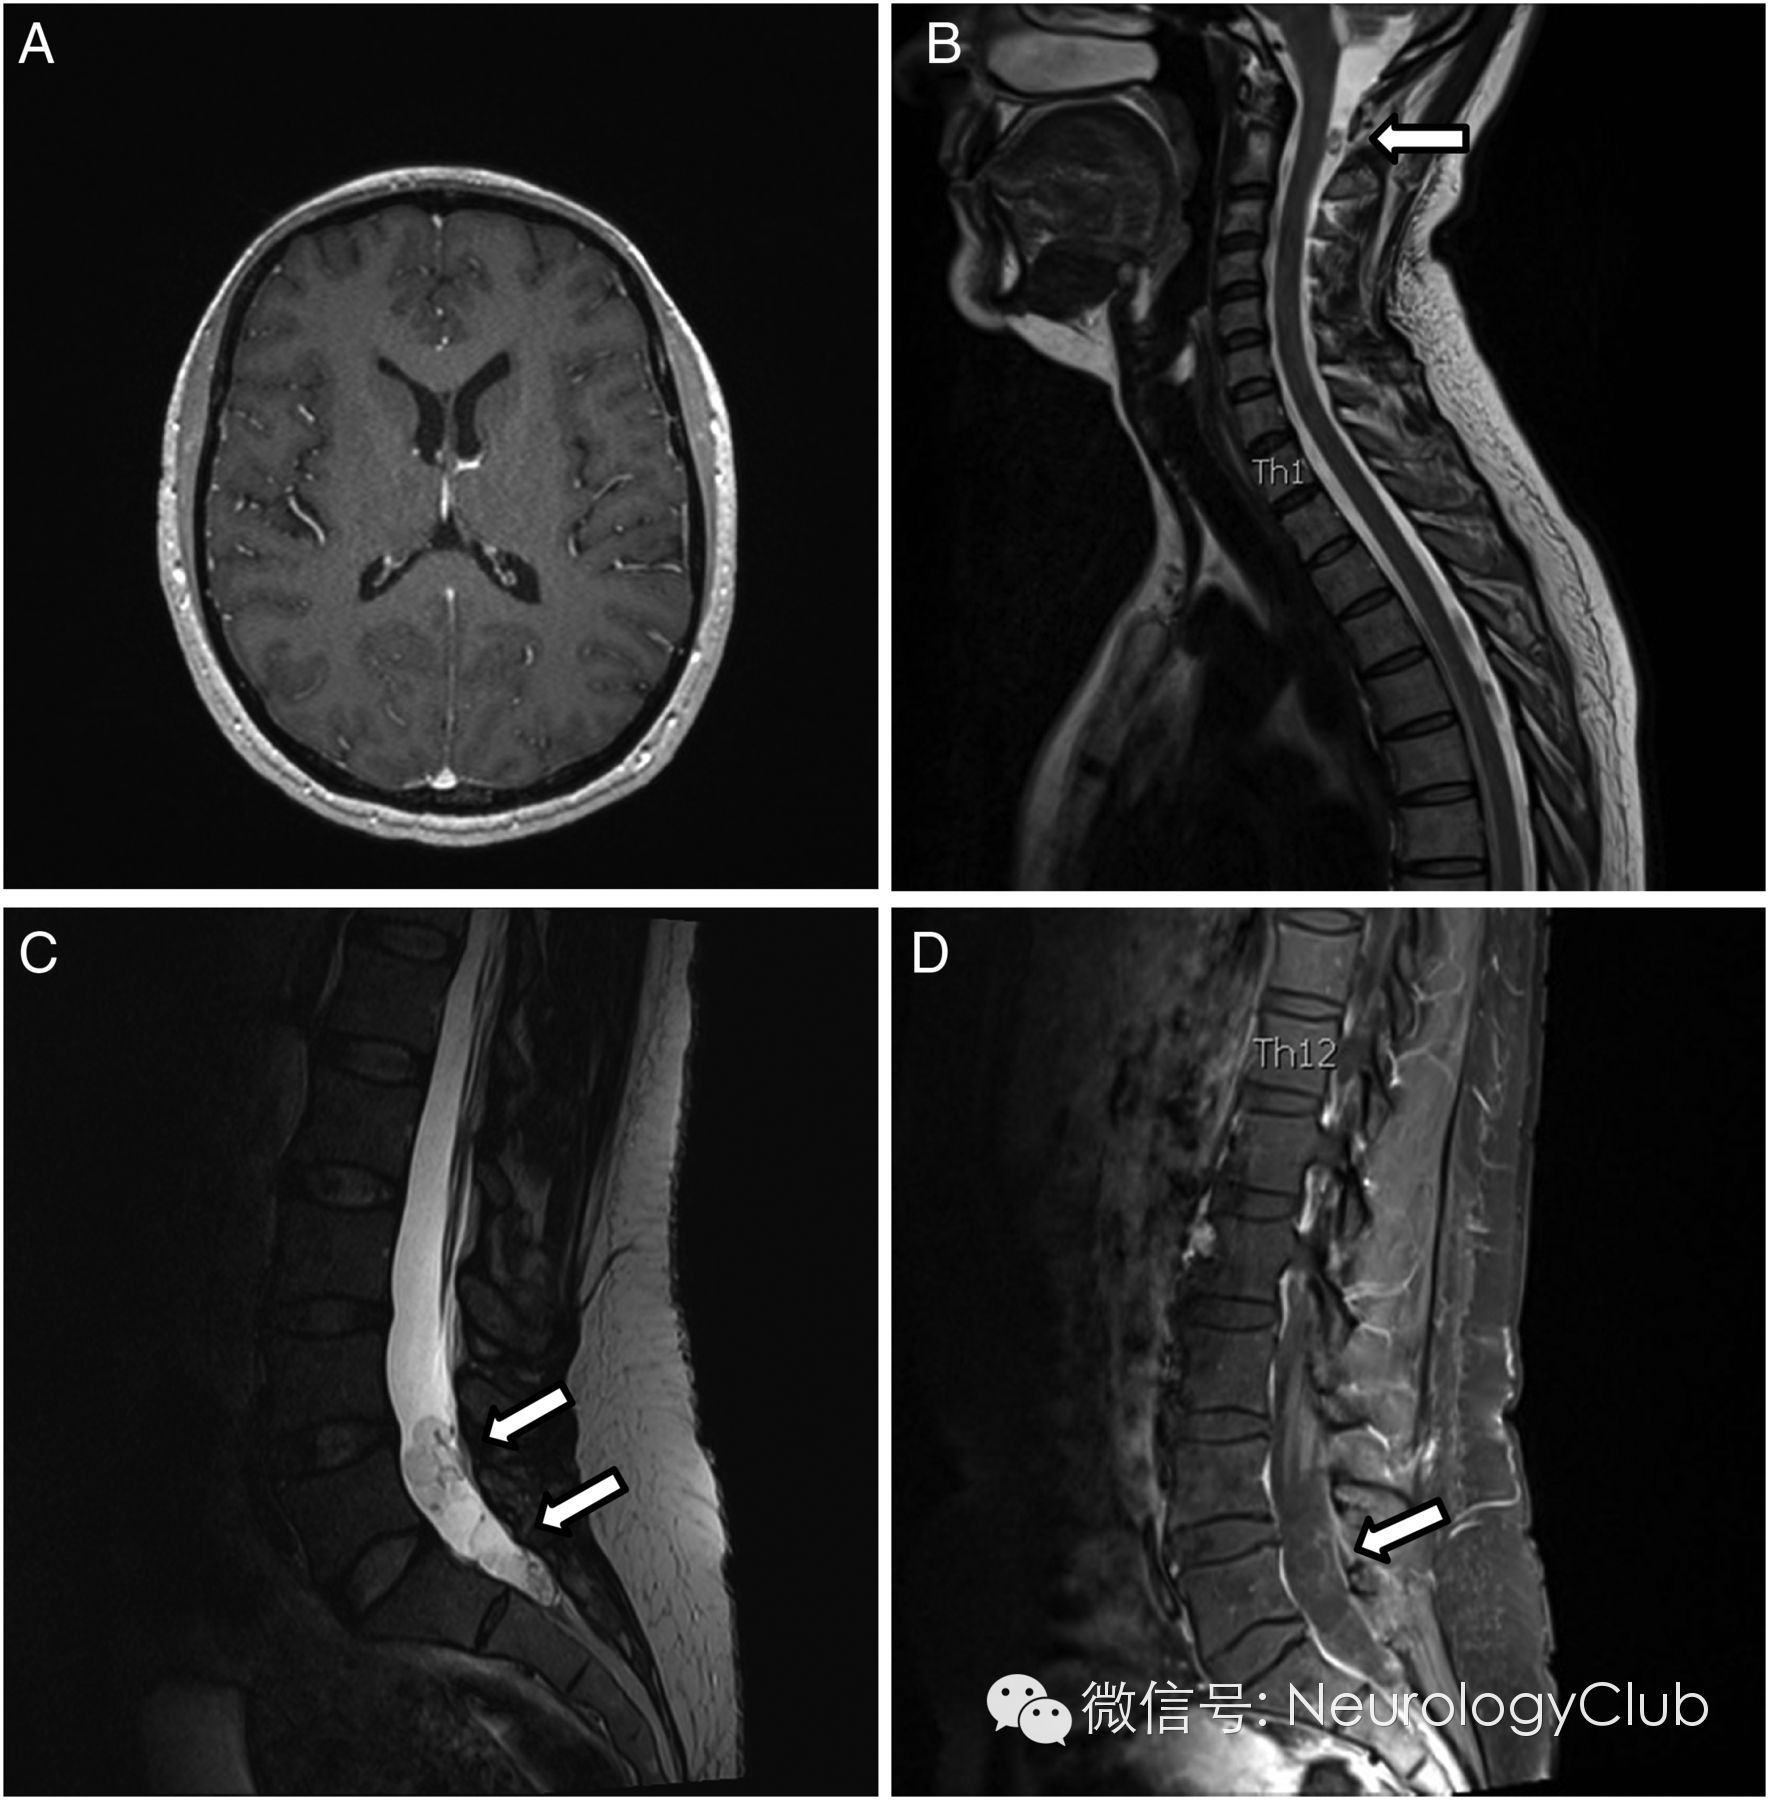

脊髓MRI见颈椎部蛛网膜下腔处有一囊性病灶,腰椎部蛛网膜下腔多发囊性病灶。增强病灶呈环形强化。

(A:T1增强;B-C:T2WI;D:T1增强)